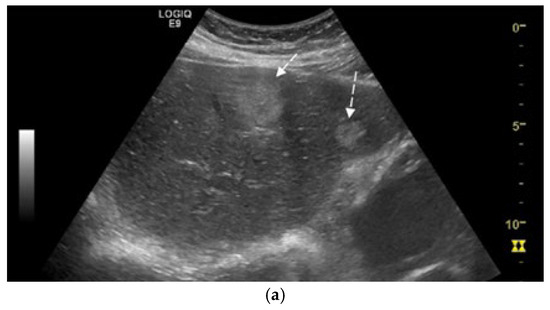

Synchronous Pulmonary and Cecal High-Grade Neuroendocrine Carcinomas Presenting as Hepatic Metastases: A Diagnostic Challenges and Literature Review

Background and Clinical Significance: Neuroendocrine neoplasms (NENs) are a group of malignancies that may remain clinically silent for many years. The presence of hepatic metastases can be the first clue leading to diagnosis. Case Presentation: We report the case of a 67-year-old man [...] Read more.

Background and Clinical Significance: Neuroendocrine neoplasms (NENs) are a group of malignancies that may remain clinically silent for many years. The presence of hepatic metastases can be the first clue leading to diagnosis. Case Presentation: We report the case of a 67-year-old man with intermittent tiredness and suspicious hepatic nodules detected on routine abdominal ultrasound. Contrast-enhanced ultrasonography showed arterial hyperenhancement with early washout, suggestive of metastases. Synchronous high-grade neuroendocrine carcinomas (NECs) of the lung and cecum were identified. Although the liver lesions were initially presumed to arise from the cecal tumor, liver biopsy immunohistochemistry was TTF-1 positive/CDX2 negative, whereas the cecal lesion was TTF-1 negative/CDX2 positive. This mutually exclusive immunophenotype confirmed two separate primary carcinomas. Given the high-grade histology, the patient received platinum-based chemotherapy and achieved a partial response. Conclusions: This case illustrates the diagnostic complexity of synchronous lesions and highlights the “mirage of the first lesion” phenomenon, in which the initially detected tumor may not represent the true primary site. A comprehensive, multidisciplinary strategy is crucial for establishing the correct diagnosis and guiding optimal management. Full article

Show Figures